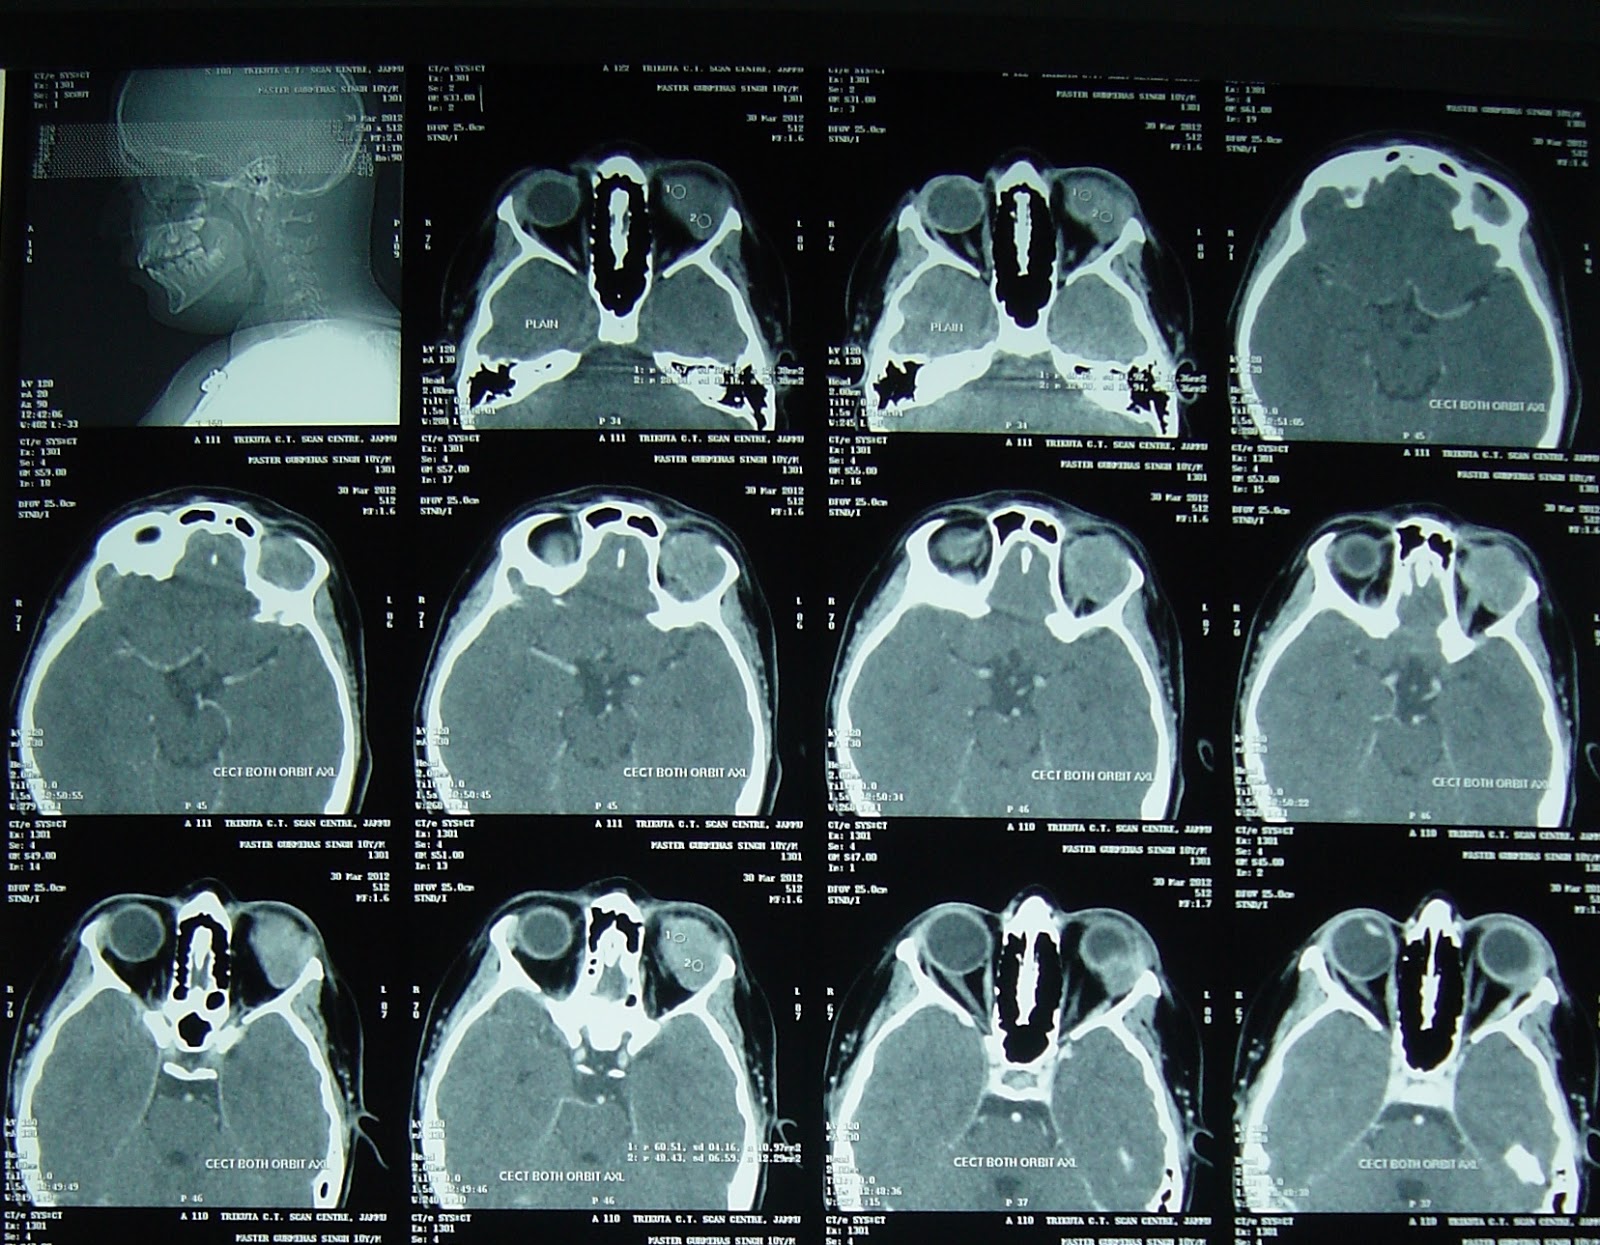

Neurosurgeon India: Orbital Rhabdomyosarcoma

neurosurgeon-india.blogspot.com

neurosurgeon-india.blogspot.com

rhabdomyosarcoma orbital neurosurgeon india mri op pre

neurosurgeon-india.blogspot.com

neurosurgeon-india.blogspot.com

rhabdomyosarcoma ct scan neurosurgeon india op pre